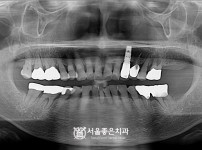

뼈이식 임플란트 5개 - 오스템 원가이드 네비게이션 임플란트

해당 게시물은 의료법 제56조에 의거하여 로그인 후 열람이 가능합니다.

구분 임플란트